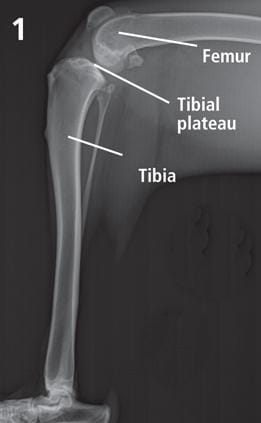

The bone just below the knee or stifle joint is the tibia and the bone above is the femur. The top of the tibia is the tibial plateau. All dogs have a sloping tibial plateau.